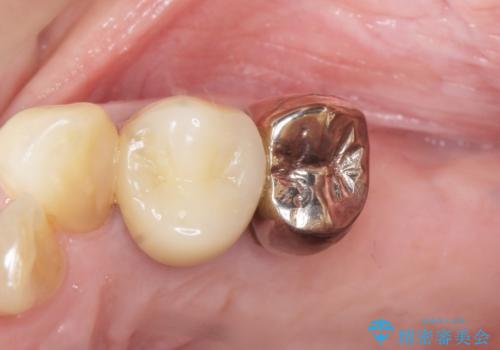

奥歯の違和感 再根管治療 40代女性

- 奥歯の違和感を主訴に来院された患者様です。

精査したところ、左上の大臼歯2本(左上67)が欠損しており、左上の小臼歯2本(左上45)は根が短く動揺があり根尖病変を認めました。

「大臼歯は入れ歯かインプラントを検討しているがまだやりたくないため、小臼歯のみを治療してほしい」との患者様のご希望により、

相談を重ねた上で小臼歯2本の再根管治療と連結補綴を行いました。

大臼歯がないため小臼歯に負担がかかりやすいことによるリスクを説明し、ご理解頂いた上で治療を行いました。